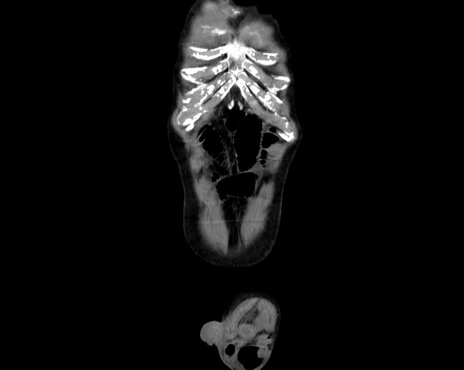

症例26(冠状断像)

横断像